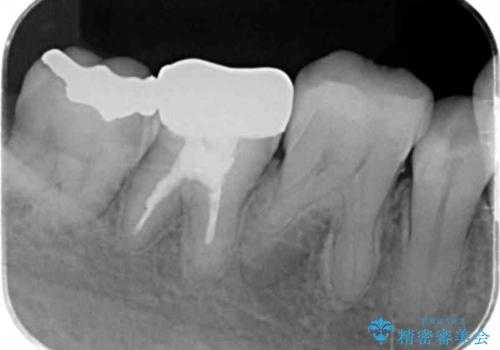

- 歯がかけたとのことで来院されました。

銀歯も白く作り替えたいとのことでしたのでセラミックインレーでの修復処置を行います。

- 右下6 セラミックインレー:77,000円費用は治療当時の料金となります